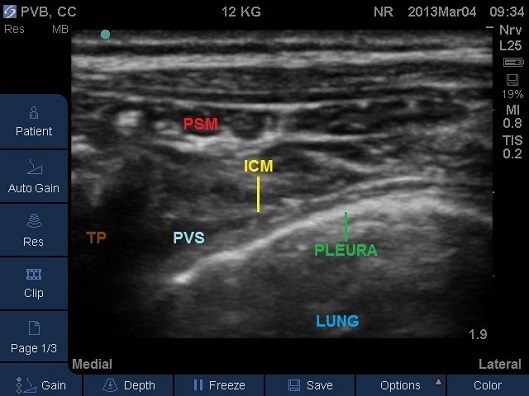

- Identify the pleura beneath (Fig 10). For the best view and a successful block you should ensure the pleura is visible as a bright white solid line with characteristic appearance of intercostal muscles above.

Fig 10. Transverse Plane Mid-Thoracic level. ICM – internal intercostal membrane, PSM – paraspinal muscles, PVS – paravertebral space, TP – tip of transverse process. Note the internal intercostal membrane is continuous with the costotransverse membrane.

- The transverse process with its acoustic shadow should be close to one end of the screen and opposite to the side of needle insertion.

- The needle should be inserted in-plane from the lateral to medial direction aiming for the junction of the pleura and the acoustic shadow underneath the transverse process (Fig 11).